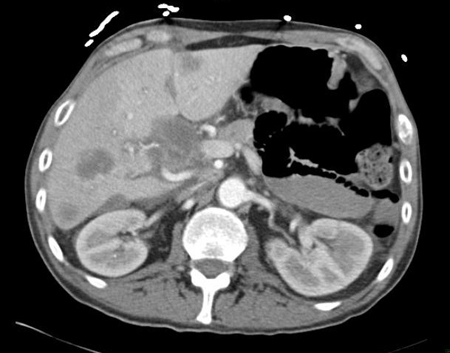

[Figure caption and citation for the preceding image starts]: TC abdominal com contraste intravenoso, revelando diversas lesões com realce no lobo hepático direito, com ascite associada; a biópsia percutânea de uma dessas lesões revelou adenocarcinoma, mas nenhum sítio primário foi identificado durante a investigação de rotina: uma manifestação típica de ASPDDo acervo pessoal do Dr. D. Cosgrove [Citation ends].

[Figure caption and citation for the preceding image starts]: Tomografia computadorizada (TC) abdominal com contraste intravenoso, revelando diversas lesões hepáticas com realce nos dois lobos hepáticos; a biópsia percutânea de uma lesão do lobo direito revelou adenocarcinomaDo acervo pessoal do Dr. D. Cosgrove [Citation ends].